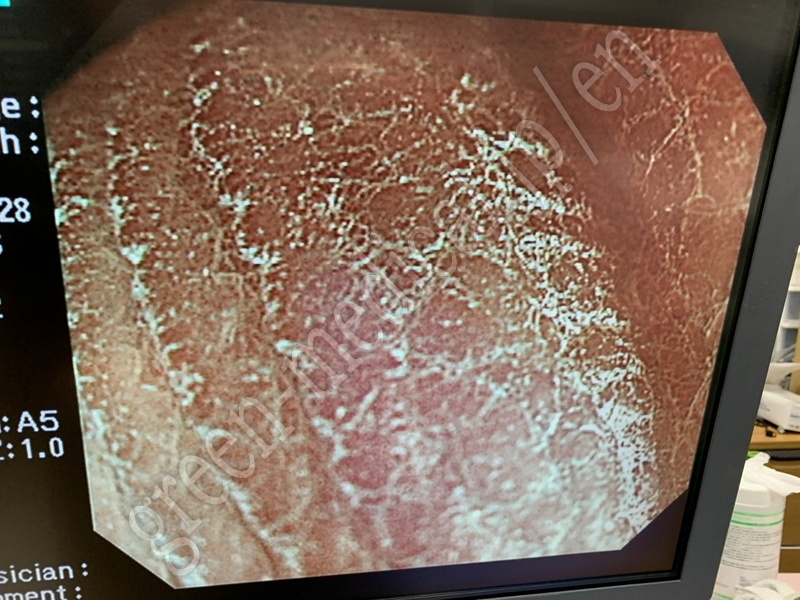

Video Colonoscope .CF-H260AZI

OLYMPUS

.CF-H260AZI

115471